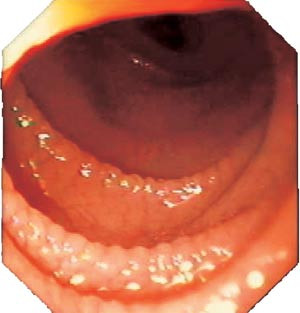

Endoskopøren bør ta minst tre biopsier, helst med stor tang, godt nede i duodenum. Biopsiene bør strekkes ut og orienteres på en papirbit med epitelet opp før formalinfiksering. Dette kan gjøres uten mikroskop. Det er vanskelig å gjøre adekvat diagnostikk på små, dårlig orienterte biopsier (16, 26). Det er grunn til å ta biopsier på vid indikasjon i enhver endoskopisk utredning av mageplager, ikke bare ved diaré. Endoskopøren bør se etter tegn som fravær av folder, furer og mosaikkmønster av slimhinnen (fig 1) (27), selv om dette ikke er diagnostisk for cøliaki (28).